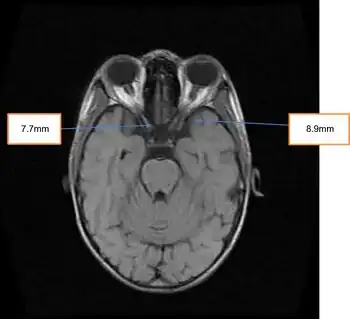

- Increased intracranial pressure manifesting as cerebral edema, papilledema, and headache[3] (may be referred to as Idiopathic intracranial hypertension)